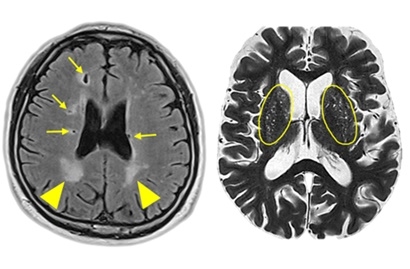

뇌경색 초기증상에 대하므로 살펴볼게요니다. 뇌에도 혈관이 있어서 피가 흐르고 있어요. 뇌에 있는 혈관이 막혀서 뇌의 일부가 손상되는 것을 뇌경색이라고 말해요. 뇌혈관이 막혀 뇌가 손상되면 장애가 발생할수 도 있으므로 뇌 연관 질환은 각별한 주의가 필요해요.

뇌에 제공되는 혈액량이 줄어들게면 뇌가 수습해야 되는 역할들을 제대로 실행해 낼 수 없게 돼요. 뇌혈류가 연속적으로 감소되면 뇌조직에 괴사가 시작되고 괴사된 뇌조직이 회복 불가능한 상태가 되면 뇌경색이라고 진단을합니다. 그러므로 뇌경색 초기증상을 알아두고 방지해억제해하시는게 중요해요.

뇌경색의 주된 이유가 되는 것은 혈전이지요. 혈전이란 혈관 속에 피가 굳어진 덩어리를 얘기하는데 이것이 혈관을 막는 것이 뇌경색에 큰 영향을 줄 수 있습니다. 평균적으로 많이 발생하는 연령대는 5~60대이지요. 뇌경색은 양쪽 뇌에 모두 나타나는는 것이 아니라 주로 한쪽 뇌에만 발생하지만, 주로 한쪽 팔다리가 마비되었다거나 얼굴 근육이 굳어버리기도 해요. 그렇기에 뇌경색 초기증상이 발생한다면 민첩하게 대응를 해야 하겠습니다.

또 뇌경색의 까닭은 혈관의 협착을 유발시키는 동맥경화증이고요. 동양에서는 뇌내동맥경화증이, 서양에서는 경동맥동맥경화증이 많이 나타나고다. 그리고 흡연, 고지혈증, 당뇨병, 고혈압, 건강에 옳지 않은 식습관, 스트레스 등도 뇌경색을 발생시키는 위험요인입니다.모든 질병에 단일 이유가 되는 것이 없듯이 뇌경색도 단일 이유가 되는 것이 아닐 수 있고요.